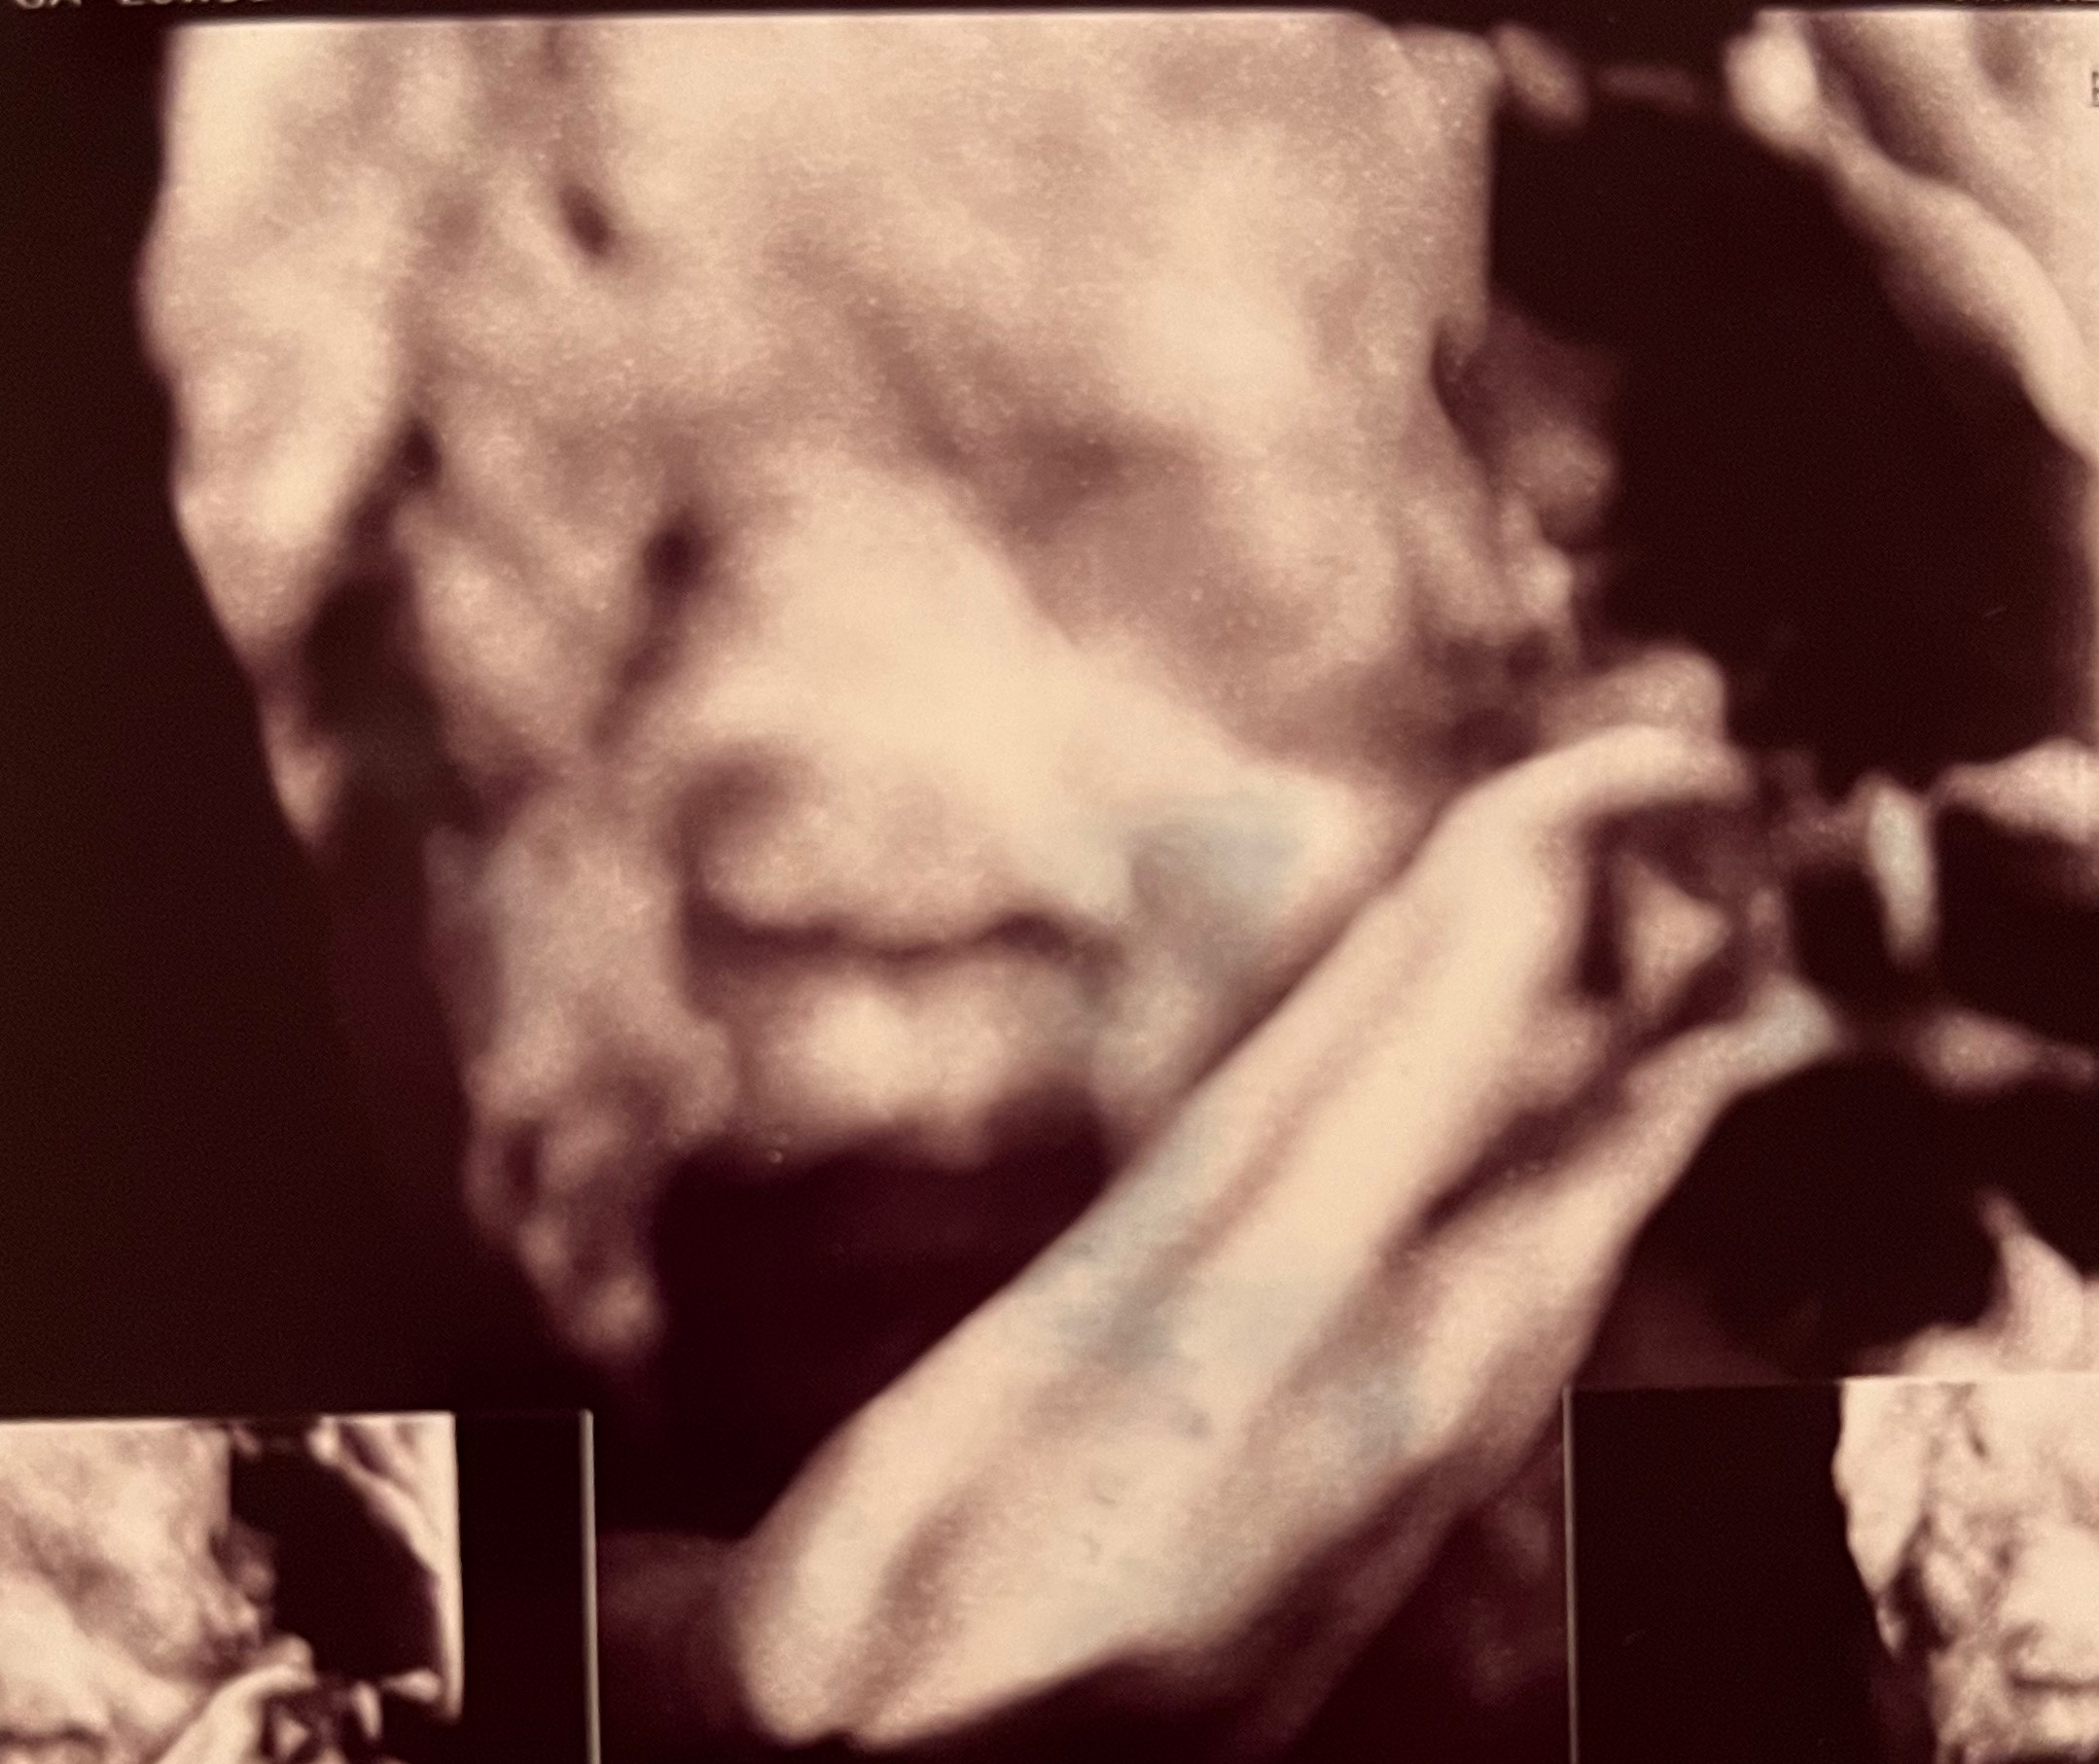

처음에 저희 아가는 한쪽 팔을 들어

턱 한쪽을 막고있는 형태로 있더라구요?

그래서 조마조마했는데

선생님이 노련하신건지, 제가 운이 좋은건지,

아기가 현재 어떤 형태로 자리잡고있는지에

기반해서 제 자세를 이리 저리 조정해주시더니

결국 ㅎㅎㅎ 보고야말았습니다!!!!

(아기얼굴 보일때의 제 자세는 왼쪽으로 누운

상태에서 거의 엎드리다시피한 각도로 벽을

잡고 지탱하는 모양새였고, 선생님은 제

오른쪽 옆구리를 거의 등뒤에서비춰서??

보시는 중이었어요, ㅎㅎㅎ)

진짜 많이 컸더라구요!

미국에서는 19-20주 2차 정밀 초음파가

끝이라서 그 이후로 처음 보는 아가였는데,

진짜 아기같은 모습이 다 갖춰져서

너무 반갑고 감격스럽고 행복했어요!

심지어 아가가 하품하는 모습까지 잡혔는데!!

심쿵사!! ♥ 진짜 너무 귀엽습니다 ㅎㅎㅎㅎ